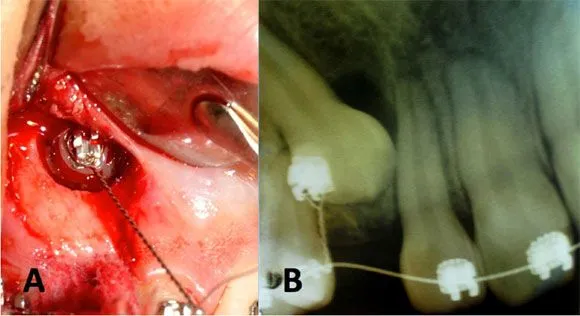

International journal of odontostomatology - Abordaje Quirúrgico ...